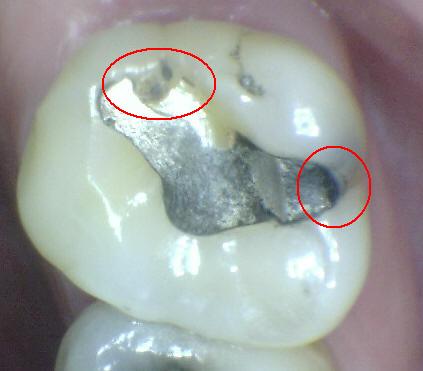

Código 5

(Caries Severa): Cavidad

detectable con dentina visible hasta la mitad de la superficie

-

Cavidad detectable

adyacente a la restauración/sellante con dentina visible

en el espacio de interfase con signos de caries tal como

se describe en el código 4, además de un espacio > 0,5

mm de ancho.

En los casos en que

los márgenes no son visibles, hay evidencia de pérdida

de continuidad en el margen de la restauración/sellante

y en la dentina, detectada por el paso de la punta de

0,5 mm de la sonda cuando se pasa por el margen de la

restauración/sellante.

Criterios para

determinar si la lesión es activa o detenida